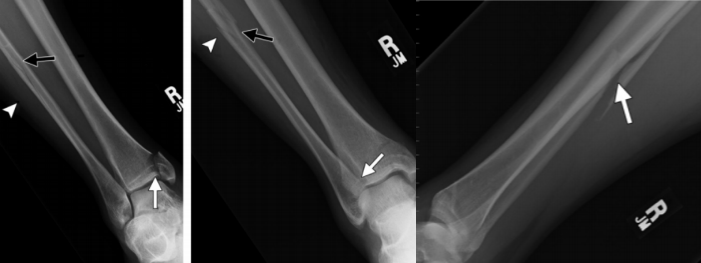

3、旋前(外翻)外旋损伤(简称 PE)

伤足处于旋前位,距骨外旋,三角韧带首先被拉紧。

旋前外旋损伤

I 度:首先发生的是三角韧带的断裂或者内踝的撕脱骨折。

I 度损伤 X 线显示:内踝水平骨折;侧位 X 线片显示后踝完整。这种损伤与旋前外展 I 度非常相似。

Ⅱ 度:距骨外旋力量继续作用于下胫腓关节,下胫腓前韧带和骨间韧带或韧带附着点撕脱骨折。

II 度损伤 X 线显示:内踝间隙增宽,提示三角韧带断裂;胫腓骨间隙增宽,提示下胫腓前联合断裂。

Ⅲ 度:腓骨骨折发生于胫骨远端关节面以上水平,甚至可以位于腓骨近端即 Maisonneuve 骨折,骨折线从前上方斜向后下方,即与旋后(内翻)外旋骨折相反。

III 度损伤 X 线片显示:内踝骨折和腓骨近端螺旋形骨折;胫腓骨间隙增宽;侧位片显示腓骨骨折,后踝无骨折。

Ⅳ 度:最后发生下胫腓后韧带断裂,或其胫骨附着点的撕脱骨折(Volkmann 骨折块)。

IV 度损伤 X 线片显示:内踝骨折;胫腓骨间隙增宽,提示下胫腓联合断裂,腓骨骨折位于下胫腓联合水平上;侧位片显示胫骨向前移位和后踝撕脱骨折。